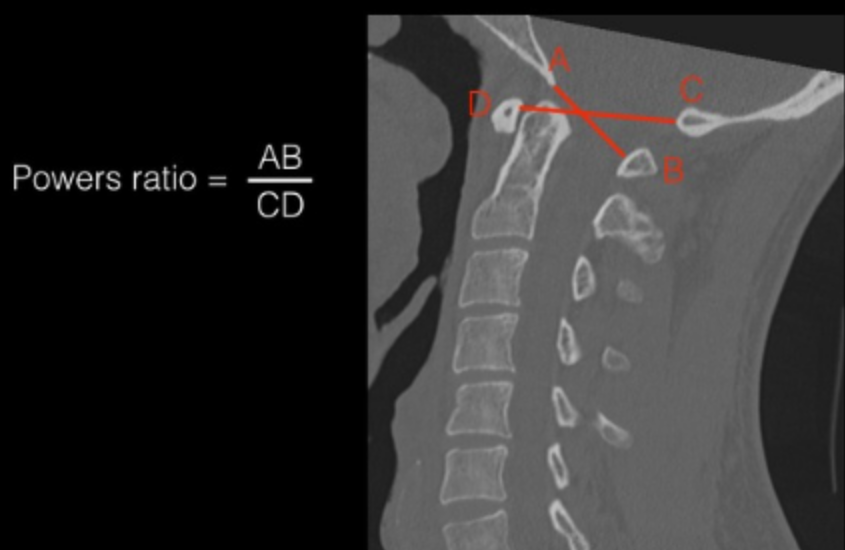

Power’s Ratio

Power’s ratio is a geometric index designed to identify anterior atlanto-occipital dislocation. It evaluates relative motion between the skull base and the atlas.

• Choose a mid-sagittal CT.

• Landmark A (Basion): The anterior margin of the foramen magnum.

• Landmark C (Opisthion): The posterior margin of the foramen magnum.

• Landmark D: The posterior surface of the anterior tubercle of C1.

• Landmark B: The anterior surface of the posterior arch of C1.

• Calculation: Measure the length of line AB and line CD. Divide AB by CD.

• Plain Radiographs: < 1.0 (The length of AB should be less than CD).

• CT Scans: < 0.9. The superior resolution of CT dictates a stricter threshold.

• Pathologic: A ratio > 1.0 is diagnostic of Anterior Atlanto-Occipital Dislocation.

A normal Powers Ratio doesn't exclude AOD, as it's specific for anterior dislocation but a poor screening for general craniocervical instability.